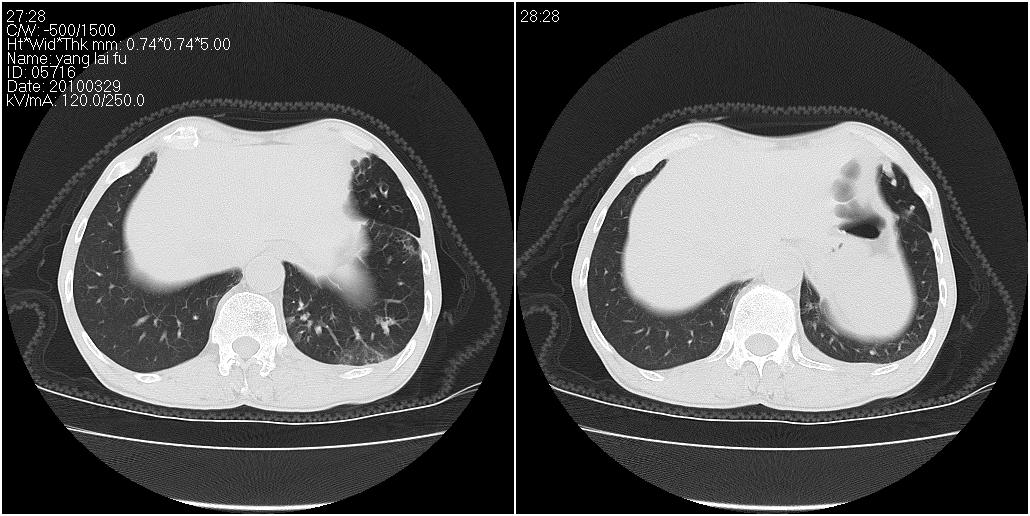

标题: CT25416:男性,70岁。胸片发现右下肺斑片状阴影 [打印本页]

标题: CT25416:男性,70岁。胸片发现右下肺斑片状阴影

以下是ct检查的情况:

考虑右肺下叶炎症可能性大?未除占位,建议增强。右下肺肺不张

右下胸壁皮下气肿。

标题: ct增强: